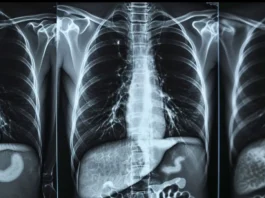

Άλλες εξετάσεις που μπορεί να χρειάζονται είναι το σπινθηρογράφημα θυρεοειδούς, το σπινθηρογράφημα νεφρών, καθώς και το σπινθηρογράφημα αιματώσεως πνευμόνων για πνευμονικές εμβολές.

Παράλληλα, η Μονάδα PET/CT του Metropolitan Hospital διαθέτει υπερσύγχρονο Τομογράφο Ποζιτρονικής Απεικόνισης που συνδυάζει τις δυνατότητες ενός συστήματος Τομογραφίας Εκπομπής Ποζιτρονίων (Positron Emission Tomography-PET) υψηλής ευκρίνειας (HD), με αυτές ενός κορυφαίου διαγνωστικού συστήματος αξονικής τομογραφίας 128 τομών. Αυτός ο συνδυασμός έχει ως αποτέλεσμα βελτιωμένη ποιότητα εικόνας και μειωμένο χρόνο εξέτασης επιτρέποντας την πραγματοποίησή της ακόμα και σε επιβαρυμένους ασθενείς.